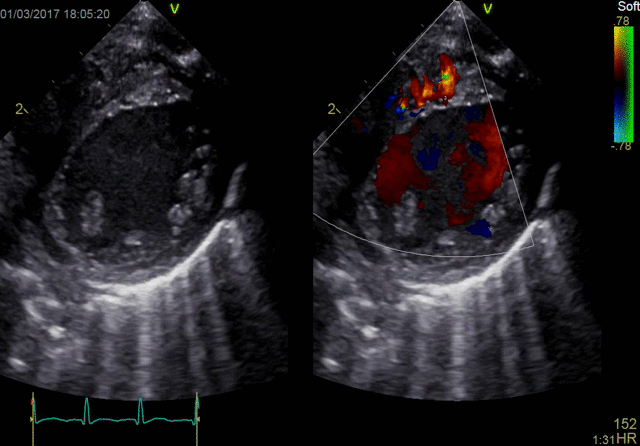

Color Flow

10T-D Color Flow